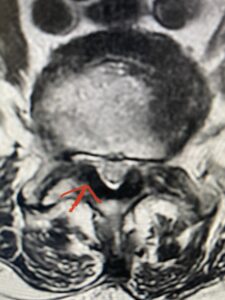

Another patient is a 62 year-old female with progressive low back pain and right leg pain and numbness that radiates to the top of her foot. She tried physical therapy and epidural injections. MRI demonstrated severe L3-4 stenosis and a grade 1 spondylolisthesis (Fig 4). There was L5-S1 and L4-5 disc collapse with modic end-plate changes. Biomechanically because of the significant degeneration of these disc spaces which stiffened the L4-S1 segment more stress was placed on the L3-4 segment, resulting in significant premature degeneration and compensatory stenosis and segmental instability. The MRI also showed pathologically, because of the slip, the L3 inferior processes were more anteriorly oriented and hence contributing to the majority of the lumbar canal compromise. Note the more sagittally-oriented facets in this case compared to the prior case (Fig 5). The patient underwent a decompressive laminectomy with attention of removing the inferior processes of L3 to fully decompress the canal. We also performed an L3-4 fusion with instrumentation (Fig 6). The patient had an uneventful postoperative course with improvement of leg pain. Of note with relief of the disabling leg pain patients are generally very happy. Patients can often manage their low back pain; it is the leg pain that they just can’t tolerate.

Fig 4: Sagittal T2-weighted lumbar MRI demonstrating L3-4 grade 1 spondylolisthesis with severe stenosis (blue arrow)